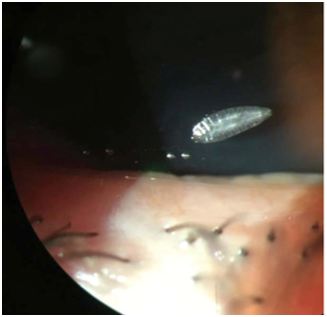

Visual acuity was 10/10 in both eyes. Slit lamp examination revealed hyperemia of the tarsal and bulbar conjunctiva and five small white translucent larvae at the inferior fornix (Figure 1). The larvae were photophobic. There was no inflammatory reaction of the anterior chamber. The fundus was normal. After application of topical anaesthesia, the larvae were removed using microsponges and saline. Topical antibiotic therapy was prescribed. After 2days, clinical signs had disappeared almost completely. The larva was identified as a first stage larva of Oestrus ovis.

Figure 1 Larva of oestrus ovis